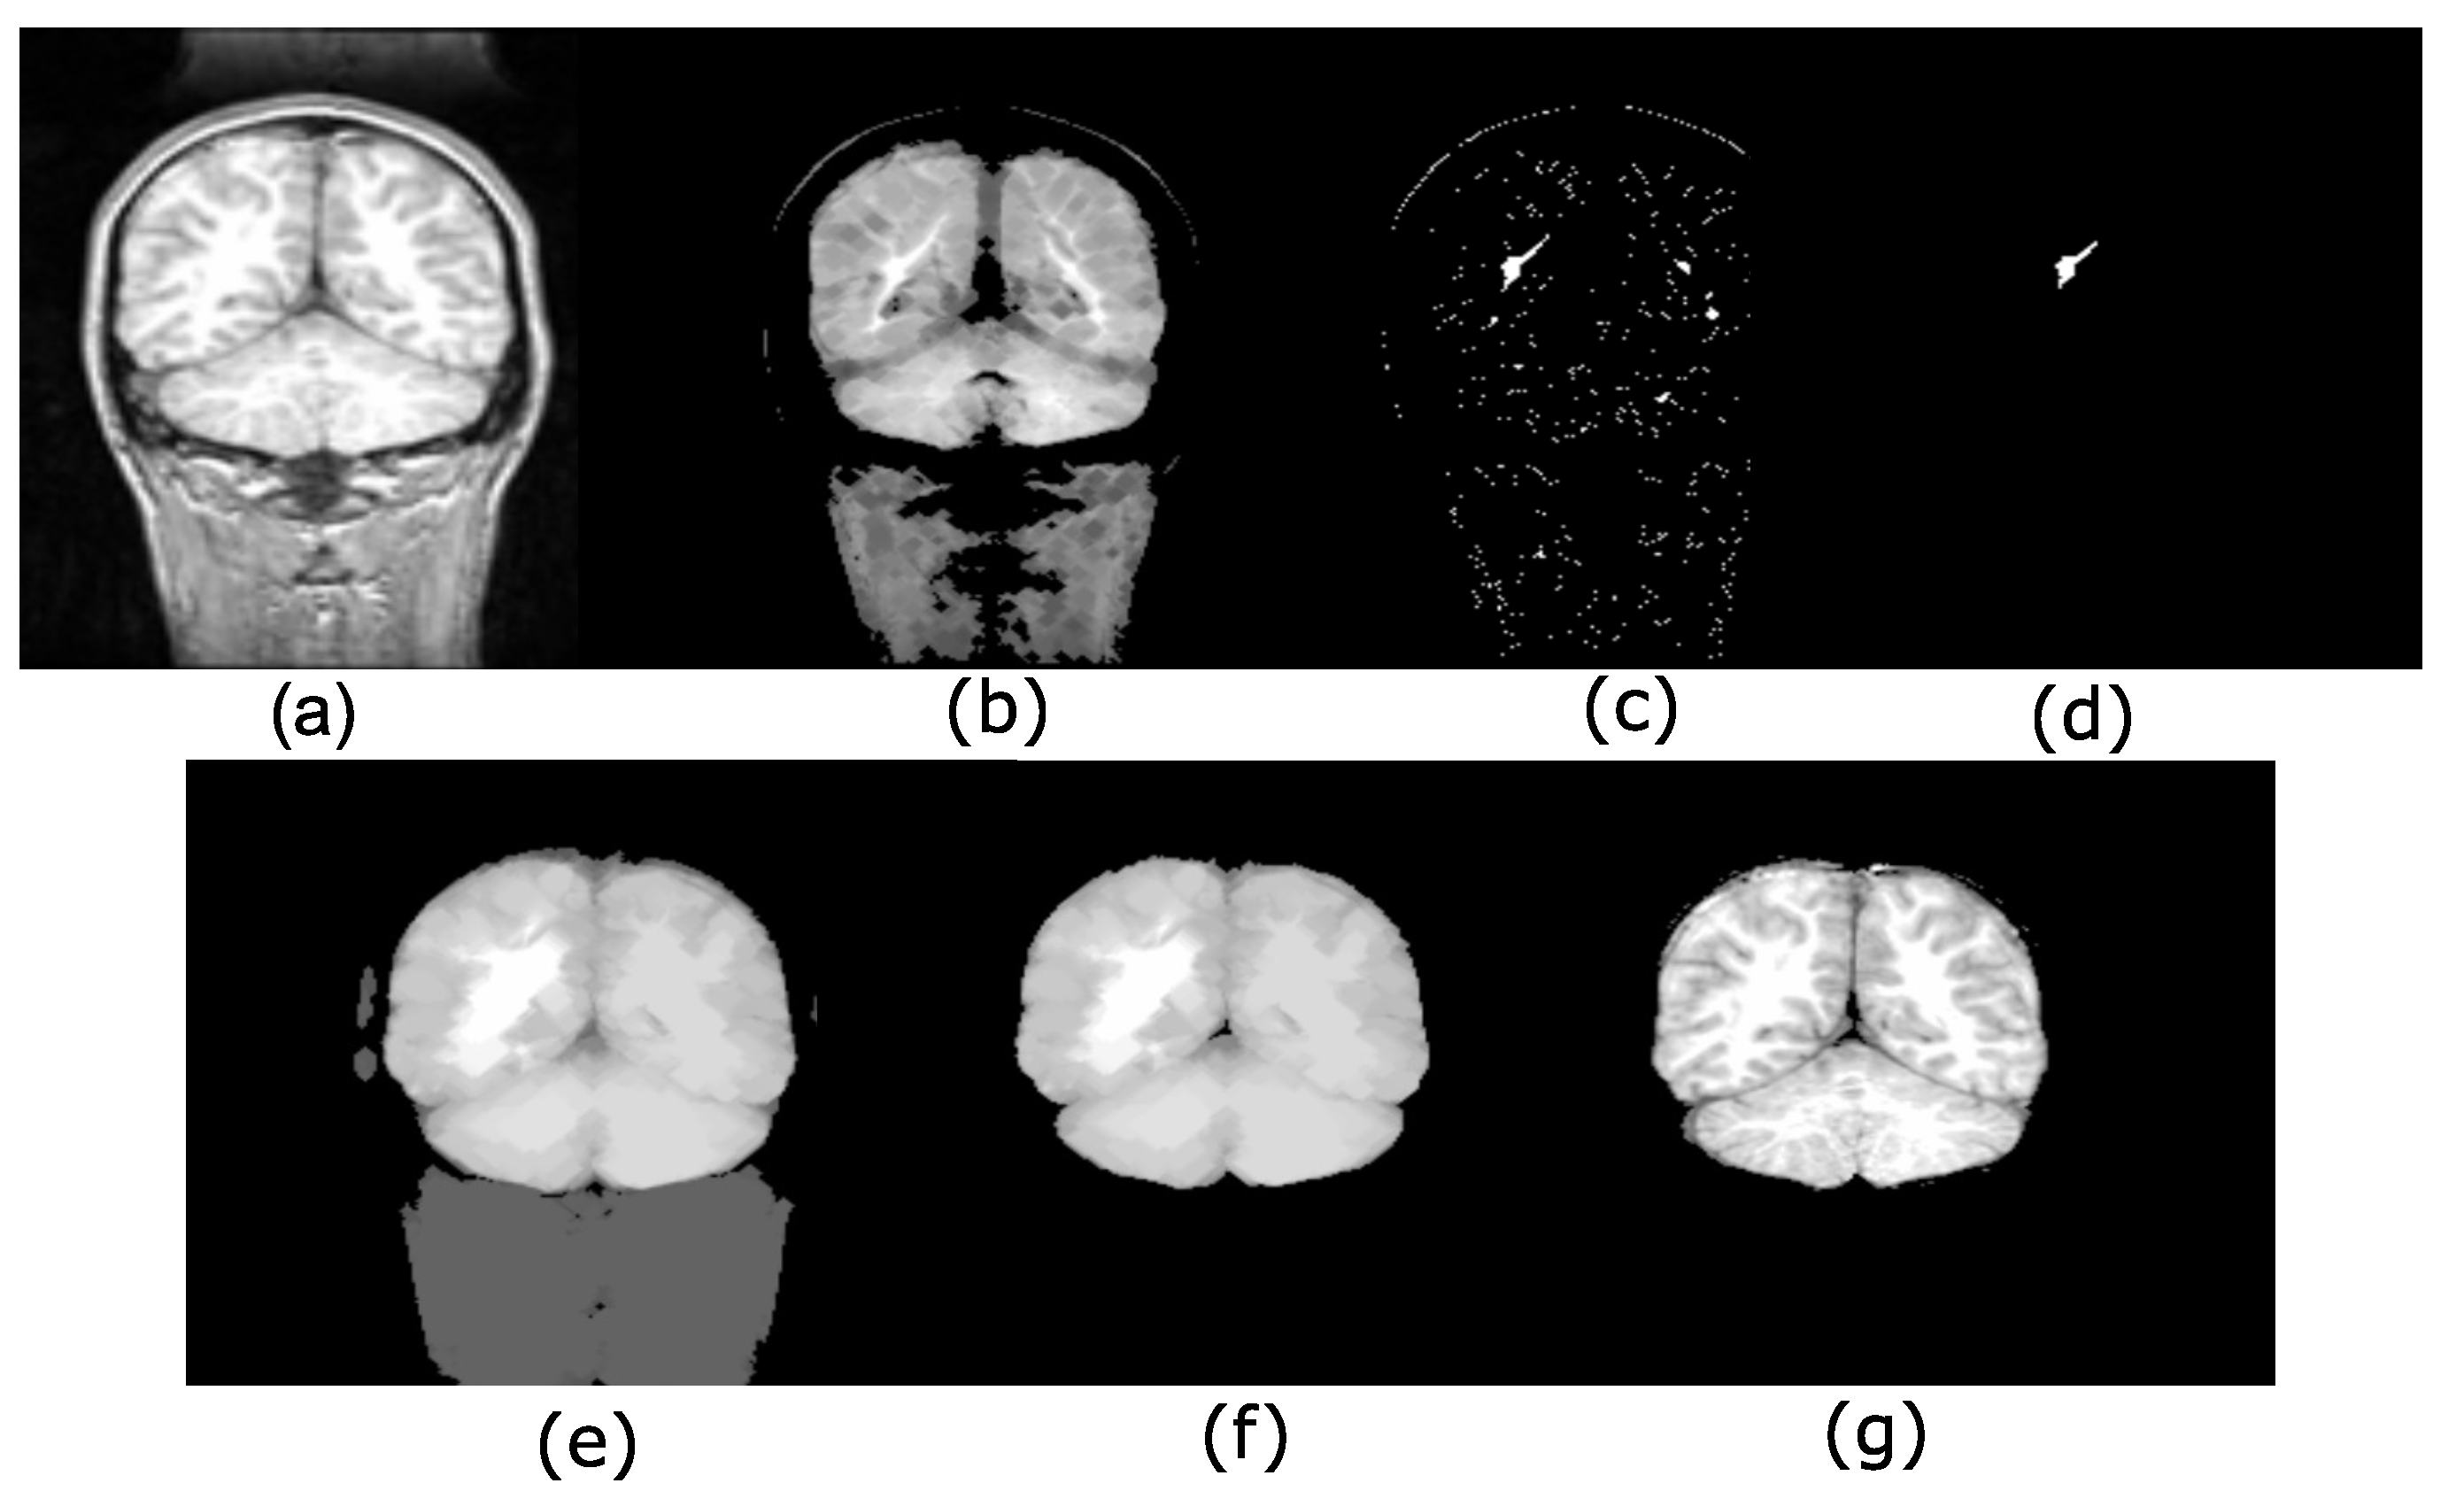

4.1. Brain Extraction Based on the Maximum Hyperconnected Function